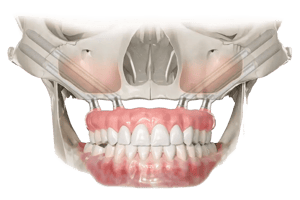

Uz pomoć naprednih kirurških tehnika i posebnih zigomatičnih, pterigoidnih, transnazalnih, subnazalnih i transsinusnih implantata, IMED Full Arch Concept® omogućuje fiksno protetsko rješenje čak i za slučajeve s potpunim gubitkom kosti čeljusti.

Koristimo posebne zygoma, pterigoidne, transsinusne i transnazalne implantate koji se sidre u čvrste koštane strukture izvan zubnog grebena. Tako je moguće ugraditi fiksni most čak i kod izrazito resorbiranog grebena, bez klasične nadogradnje kosti.

Ugradnja pod kutom omogućuje zygoma implantatima da:

- Zaobiđu sinuse

- Dosegnu čvrstu, gustu jagodičnu kost koja pruža veću stabilnost

- Ravnomjerno raspodijele žvačnu silu

- Omoguće fiksnu protetsku nadogradnju bez potrebe za nadogradnjom kosti ili sinus liftom

Zbog toga zygoma implantati predstavljaju idealno rješenje za pacijente s teškom atrofijom gornje čeljusti, omogućujući fiksne zube čak i u najtežim slučajevima gdje klasični implantati nisu mogući.